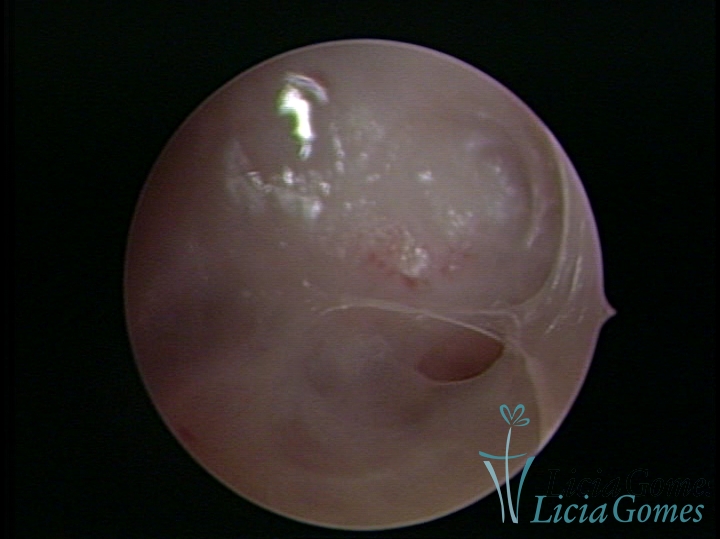

FIBROUS SYNECHIA

Uterine synechiae are scars (adherence) between the surface of the uterine walls, which may occur after the surgical procedure, uterine curettage, or after an inflammatory process in the uterine cavity (endometritis), which may lead to menstrual changes, infertility and obstetric complication such as abortion and premature birth.

• SINÉQUIA TIPO FIBROSA